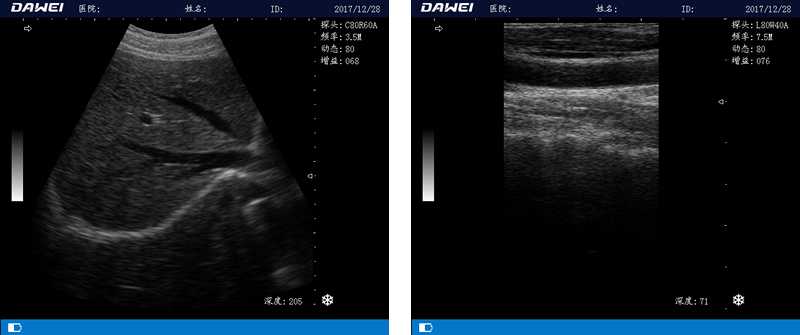

筆記本全數(shù)字超聲診斷儀

1.優(yōu)質(zhì)的數(shù)字成像技術(shù),圖像更清晰